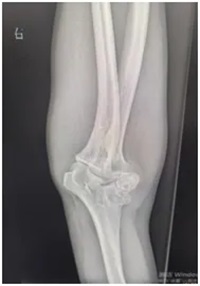

刘师傅赶忙来到郑州大学第五附属医院骨科一病区就诊。接诊医生为他安排了肘关节X线和上肢肌电图检查:

X线显示:肘关节存在明显畸形改变;

同时,刘师傅的右肘关节也出现了问题——不仅伸屈活动不灵活,外观还明显向外侧撇,正常人的肘关节本身会有一点生理性外翻(女性约10~15°,男性约5~10°左右),可医生测量后发现,刘师傅的肘关节外翻角度竟然达到了30°左右,远远超出了正常范围!